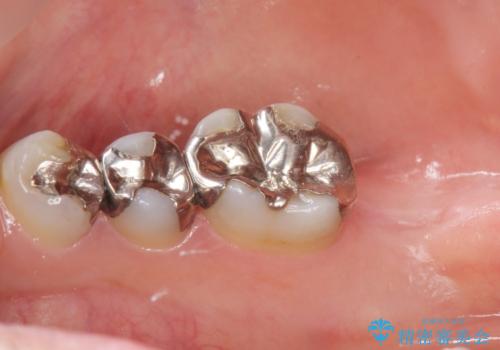

- インプラントをできるだけ安く入れたいとご希望され来院された患者様です。

予算は抑えたいが確実でしっかりとした治療を受けたいとの事でした。

レントゲン及びCTを撮影し骨の状態を確認したのち、アルファタイトインプラントによる治療を行いました。